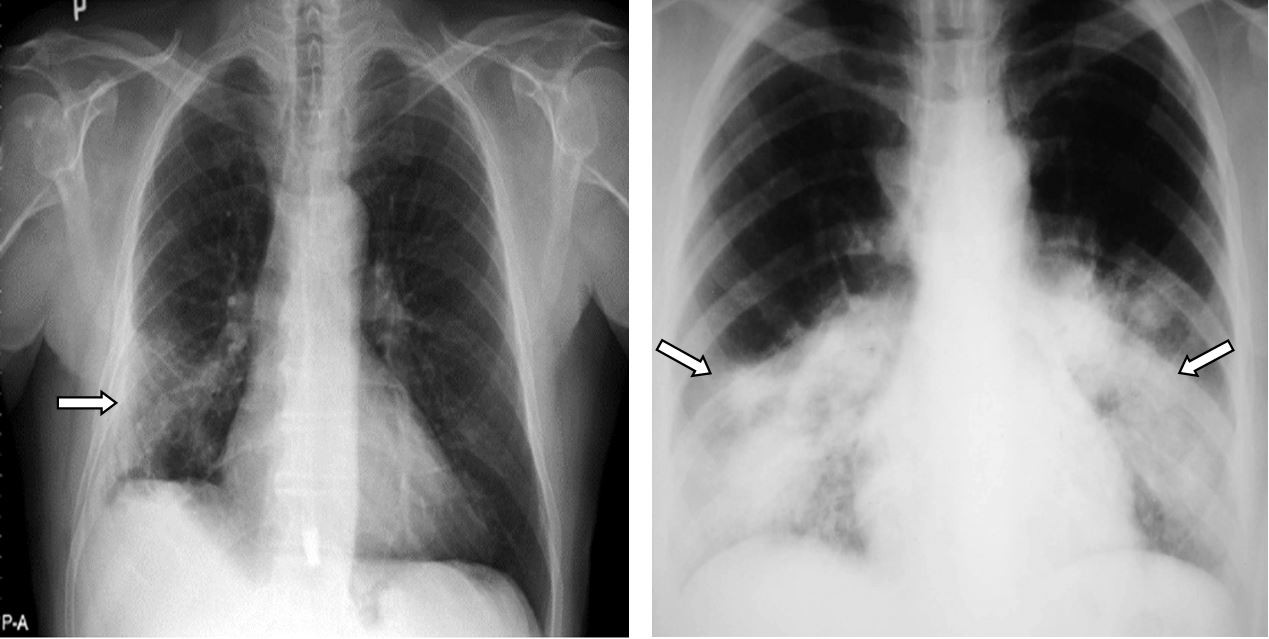

Nhiều F0 dù triệu chứng nhẹ nhưng vẫn quá lo lắng, đi chụp chiếu phim sau khi khỏi bệnh (ảnh minh họa)

Tương tự là trường hợp gia đình chị Trần Thu Hương (trú tại Tây Hồ, Hà Nội), cả nhà chị cùng mắc trong thời điểm Hà Nội “nóng” lây nhiễm Covid-19 với biến chủng Omicron. Triệu chứng chung là sốt và ho như cuốc kêu chừng 3 ngày đầu, rồi giảm dần trong những ngày tiếp theo. Chị Hằng cho hay: “Âm tính được chục ngày, gia đình đi tầm soát hậu Covid-19, bác sĩ cho hay các chỉ số đều rất ổn, đặc biệt là phim phổi rất "đẹp”